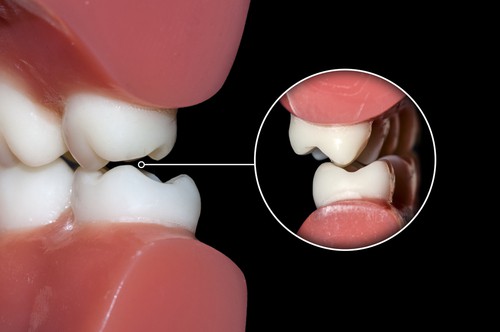

The physical results of long-term teeth grinding can be detrimental to your dental health if left unchecked. Teeth can become chipped, cracked, and even loosened, and tedious pain in your jaw muscles is almost guaranteed. Because of the consistent pressure applied from grinding your teeth every night many people develop neck or ear pain, headaches, as well as a sensitivity to food and drinks that are hot, cold, sweet, or sour.

Long-term use of a mouth guard can alleviate the pressure of the grinding, resulting in better quality sleep and less jaw pain. However it is not recommended that you stop using the guard should you feel an improvement, unfortunately this is an issue that often requires life-long maintenance.

The highly trained team at our Perth dental clinic is perfectly placed to help reduce the pain and wear that happens to your teeth and jaw when you grind your teeth. As experts in preventative dentistry, we can easily carry out an examination to see whether we recommend getting one of our top quality occlusal splints. These mouthguards, worn at night, protect your teeth from future wear as well as safeguard any dental work you may have had, or will have. Invest in your smile today and book an appointment with us, your friendly, local dentist in Victoria Park, for a thorough check-up.